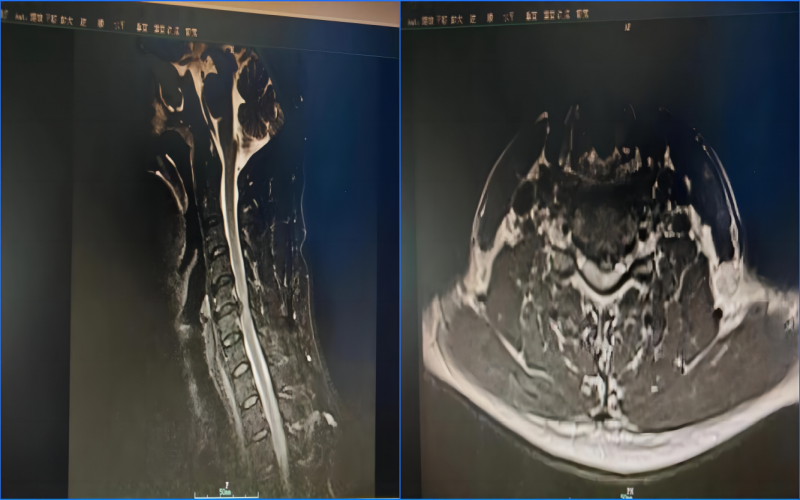

3月16日,我院脊柱骨科在蘭大二院羅志強教授指導下成功開展一例頸5-6椎間盤突出頸椎前路椎間盤切除減壓椎間盤融合術(ACDF),手術過程順利?;颊咝g后24小時后下地行走,雙上肢疼痛麻木乏力、下肢無力癥狀完全消失。此例手術是我院首例頸椎(ACDF)手術,標志著脊柱骨科又一次取得了新進展、新突破。 患者王某,男,37歲,3月6日因車禍傷致頸部、胸部疼痛,伴四肢麻木、無力,活動受限。入院后完善相關檢查,影像學檢查回報提示:頸椎生理曲度變直,頸4-6椎體邊緣骨質增生變尖,頸4/5、頸5/6椎間盤向后突出,相應硬膜囊受壓,骨性椎管前后徑見。結合病史、查體,診斷:1.頸部脊髓功能損傷C6;2.頸部脊髓水腫;3.頸椎間盤突出;4.頸椎退行性病變;5.全身多處軟組織損傷 手術采取全麻仰臥位,歷時2小時順利結束,術后患者清醒后即刻感覺雙上肢疼痛麻木乏力癥狀好轉。復查見椎體后緣骨贅磨除徹底,減壓充分?;颊呒凹覍賹κ中g非常滿意,感慨地說:“感謝酒泉市中醫(yī)醫(yī)院脊柱骨科團隊為我們患者提供了精準、安全、有效的治療方法。” ACDF是治療頸椎疾病的經(jīng)典術式,經(jīng)過臨床廣泛應用,其療效顯著,具有創(chuàng)傷小、出血少、并發(fā)癥少等優(yōu)點。與后路手術相比,前路手術可以直接解除來自脊髓前方的壓迫因素,如退變的椎間盤組織、椎體后緣骨贅、肥厚或骨化的后縱韌帶以及增生的鉤椎關節(jié)等;椎間隙植骨可有效恢復椎間隙高度、維持頸椎生理彎曲度、重建病變節(jié)段的穩(wěn)定性,符合頸椎的病理生理特點,一直是治療頸椎疾患的主流術式。 隨著微創(chuàng)理念的深化,微創(chuàng)技術的不斷進步,我院脊柱骨科堅持團結奮進、守正創(chuàng)新,圍繞“脊柱手術精細化、微創(chuàng)化”的發(fā)展思路,秉承術后加速康復理念,堅持創(chuàng)新和發(fā)展,在脊柱微創(chuàng)治療領域方面積累了豐富的臨床診療經(jīng)驗,不斷創(chuàng)新和挑戰(zhàn),以精湛的技術,造福廣大脊柱疾病患者。 脊柱骨科 就診地址:酒泉市中醫(yī)醫(yī)院四樓脊柱骨科 咨詢電話: 一樓門診部:0937-2669161